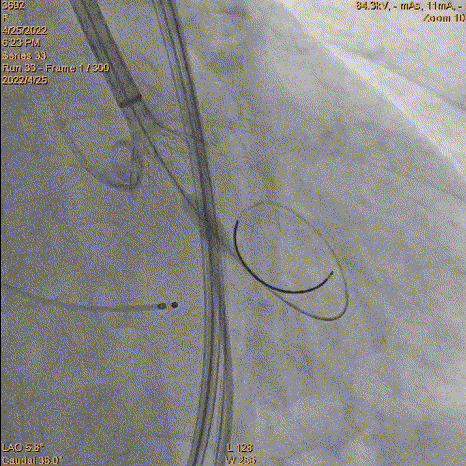

重新过瓣

瓣膜过瓣

5、瓣膜定位和释放:参考猪尾中段1/3作为起始点。由于猪尾未到达窦底,参考1/2,参考Cusp overlap角度。造影确认位置,开始释放,1/4圈满满释放前1/3,起搏140bpm,压力逐步下降。

瓣膜定位评估

瓣膜释放

评估深度

评估深度-过深

6、瓣膜回收和再释放:到达2/3后小弯侧较深,经多角度评估评估较深,起搏回收再次释放。